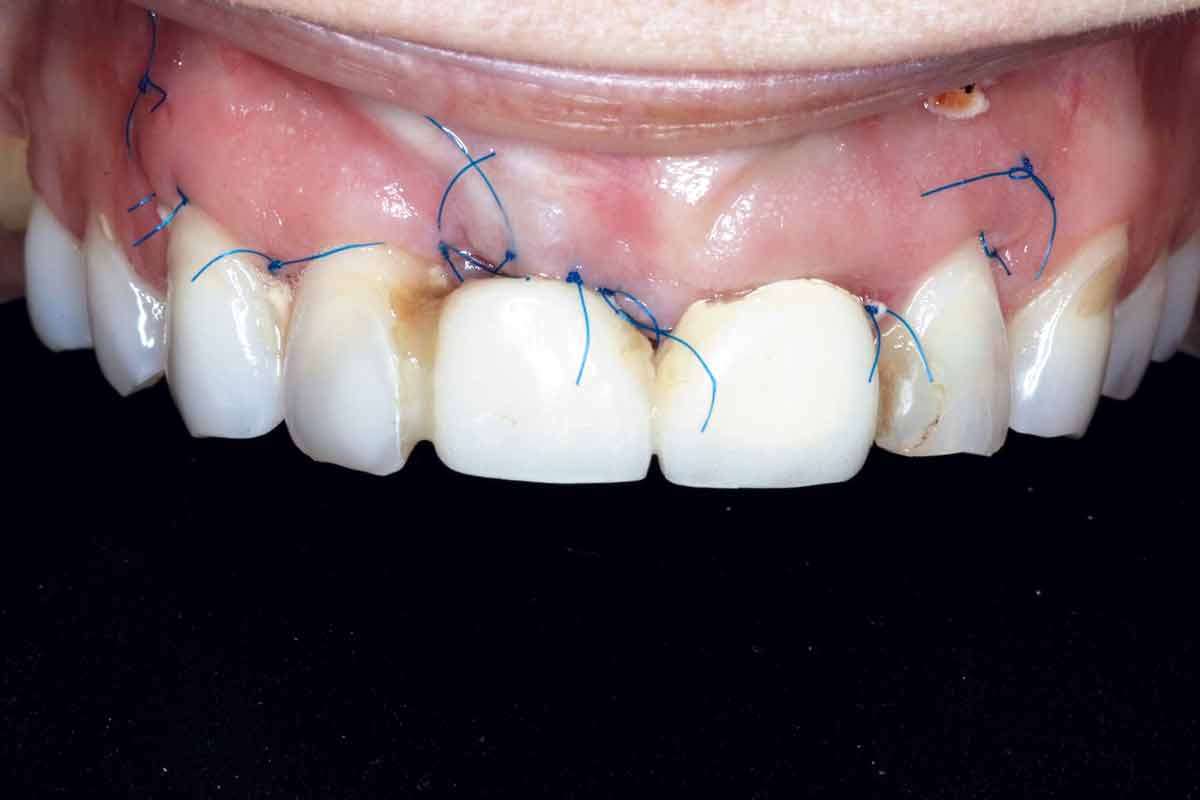

Implant placement and bone augmentation in the aesthetic zone using maxgraft® and permamem® - Dr. A. Puišys

Implant placed in the deficient site. permamem® in place for covering.

Initial situation - A young female 34 years old lost her front teeth in an surfing accident and she had a 5 unit bridge supported by her upper left lateral and right canine. The restoration failed and both supporting crowns have exposed and leaking margins.